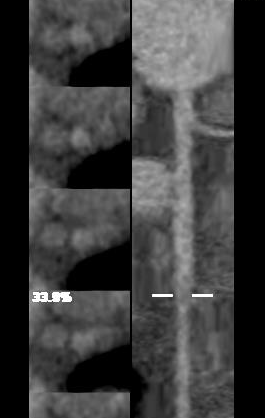

ge ct有哪些型号不怕超重 自由呼吸 | GE Revolution CT显神奇,实现完美冠脉CTA检查!_https://www.jmylbn.com_新闻资讯_第11张

ge ct有哪些型号不怕超重 自由呼吸 | GE Revolution CT显神奇,实现完美冠脉CTA检查!_https://www.jmylbn.com_新闻资讯_第12张

RCA右冠状动脉多发软斑块并管腔轻度狭窄

冠状动脉CTA检查精准找出胸痛元凶

临床医师结合影像结果,迅速明确诊断,

给予对症改善心脏循环治疗,

4天后张先生好转出院。